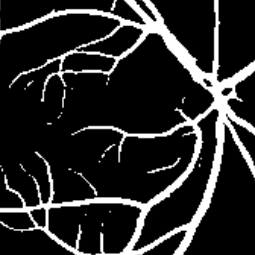

Semantic segmentation of blood vessels is an important task in medical image analysis, but its progress is often hindered by the scarcity of large annotated datasets and the poor generalization of models across different imaging modalities. A key aspect is the tendency of Convolutional Neural Networks (CNNs) to learn texture-based features, which limits their performance when applied to new domains with different visual characteristics. We hypothesize that leveraging geometric priors of vessel shapes, such as their tubular and branching nature, can lead to more robust and data-efficient models. To investigate this, we introduce VessShape, a methodology for generating large-scale 2D synthetic datasets designed to instill a shape bias in segmentation models. VessShape images contain procedurally generated tubular geometries combined with a wide variety of foreground and background textures, encouraging models to learn shape cues rather than textures. We demonstrate that a model pre-trained on VessShape images achieves strong few-shot segmentation performance on two real-world datasets from different domains, requiring only four to ten samples for fine-tuning. Furthermore, the model exhibits notable zero-shot capabilities, effectively segmenting vessels in unseen domains without any target-specific training. Our results indicate that pre-training with a strong shape bias can be an effective strategy to overcome data scarcity and improve model generalization in blood vessel segmentation.